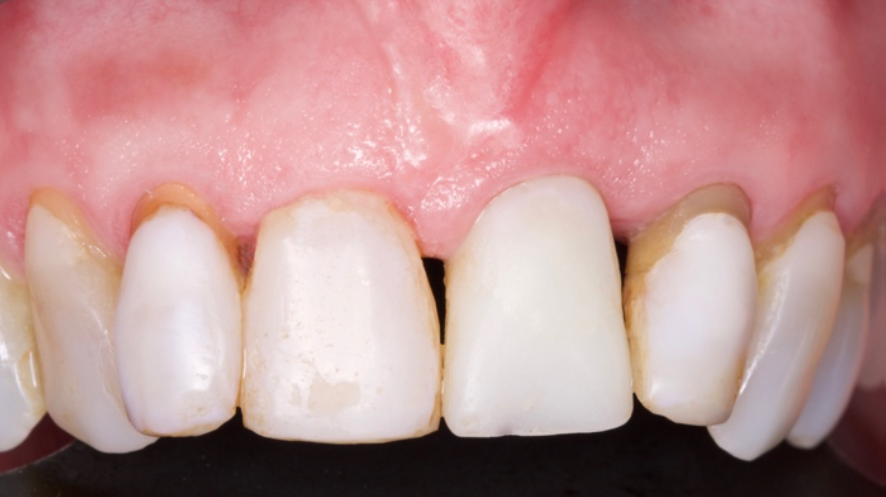

O objetivo deste relato de caso é mostrar a utilização do implante de diâmetro reduzido em região anterior de maxila com limitação óssea, respeitando a anatomia do processo alveolar e consequentemente utilizando um componente angulado para corrigir a posição da saída do parafuso para confecção de uma prótese aparafusada.

Ao contrário dos métodos tradicionais de colocação de implantes que requerem um período de cicatrização após a extração do dente, a colocação imediata do implante permite que o implante seja inserido imediatamente após a extração. Isso elimina a necessidade de um procedimento cirúrgico separado e reduz a duração total do tratamento para os pacientes. Além disso, a colocação imediata do implante pode levar a melhores resultados estéticos, pois a preservação de tecidos moles e duros é mais bem-sucedida em comparação com a colocação tardia do implante. A preservação desses tecidos pode contribuir para um resultado final com aspecto mais natural e funcional.

O planejamento no tratamento de implante imediato deve incluir uma avaliaçãocompleta do alvéolo de extração, osso circundante e tecidos moles. Essa avaliação ajuda a determinar o tamanho, o tipo e a técnica de colocação do implante.

Ao considerar esses fatores e seguir os protocolos adequados, os profissionais podem obter resultados bem-sucedidos com a colocação imediata de implantes em alvéolos frescos.